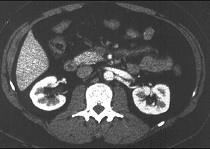

问题 男性,40岁,半年前因双下肢麻木、发凉、疼痛于外院诊断血栓闭塞性脉管炎,近1周腹痛、腹胀,以中下腹为著,呈阵发性加剧就诊,行CT增强扫描,如图所示 ( )

选项 A.胰头部略膨隆,内部密度不均。 B.门静脉及肠系膜肠系膜上静脉增宽。 C.门静脉及肠系膜静脉内见条形充盈缺损。 D.考虑为胰头癌。 E.考虑为门静脉及肠系膜内血栓形成。

答案 ABCE